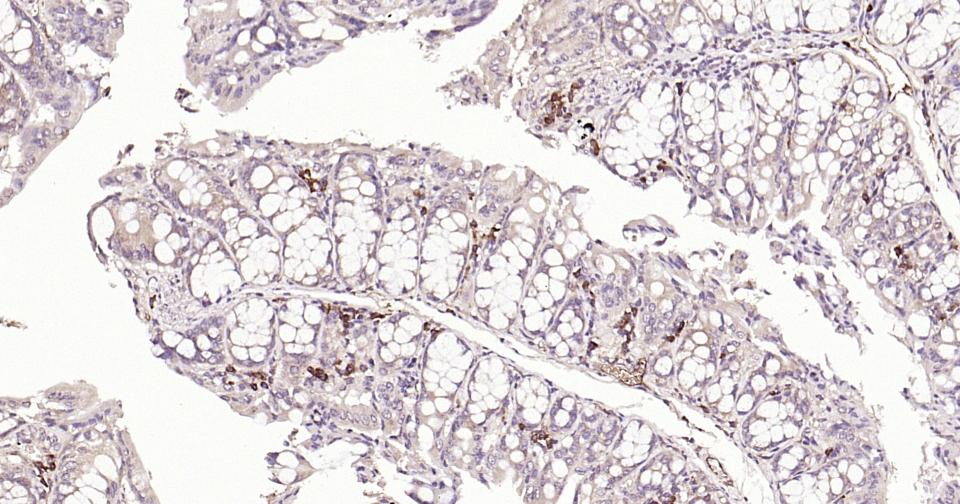

| 应用 | 已检合格种属 | 预测种属 | 推荐稀释比例 |

|---|---|---|---|

| IHC-P | Human, Mouse, Rat | 1:100-500 | |

| IHC-F | Human, Mouse, Rat | 1:100-500 | |

| IF | Human, Mouse, Rat | 1:100-500 |

交叉反应: Human, Mouse, Rat